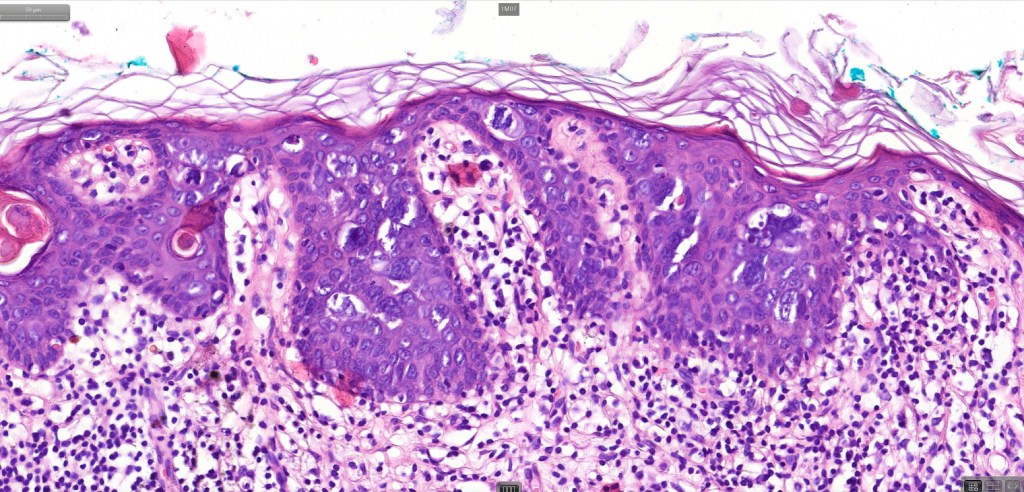

•Hyperkeratosis, parakeratosis & acanthosis

•Full thickness dysplasia (carcinoma in situ) involving the epidermis and intraepidermal adnexal elements

•Loss of maturation, nuclear pleomorphism, marked mitotic activity +/- abnormal forms

•Dyskeratosis & apoptosis